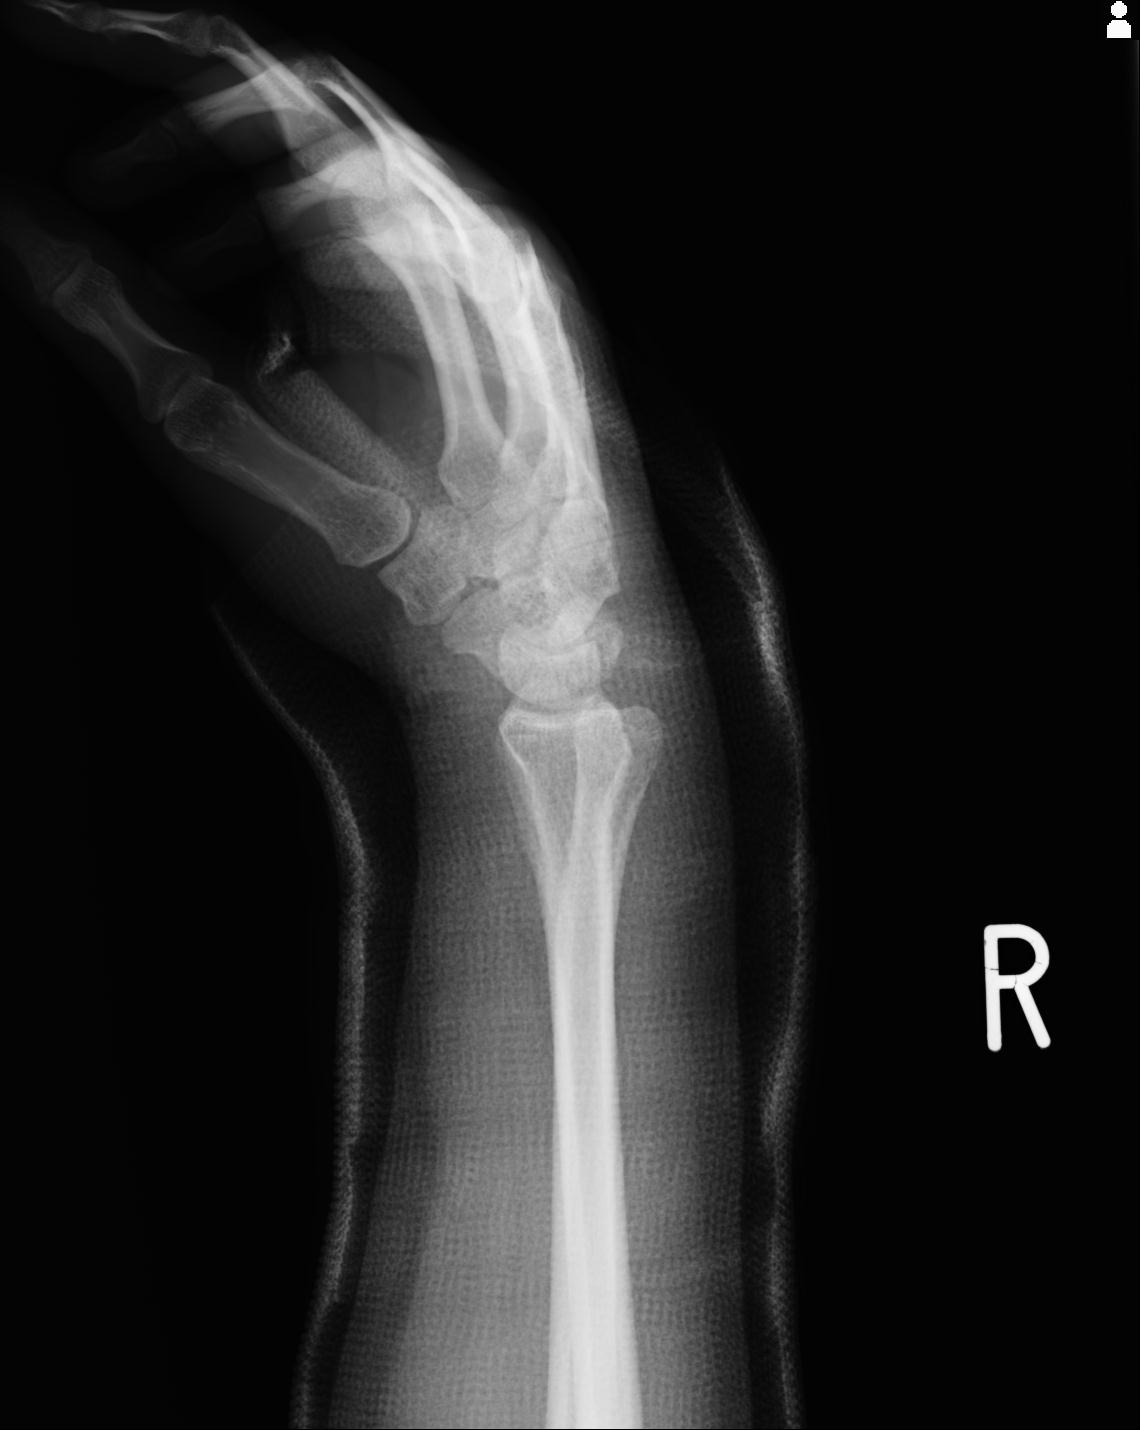

46666 1/23 両股正面+軸と右手関節 2R 76歳女性 右橈骨遠位端

46666 1/28 両股正面+軸と 1/26 右手関節 2R 76歳女性 右転子部骨折